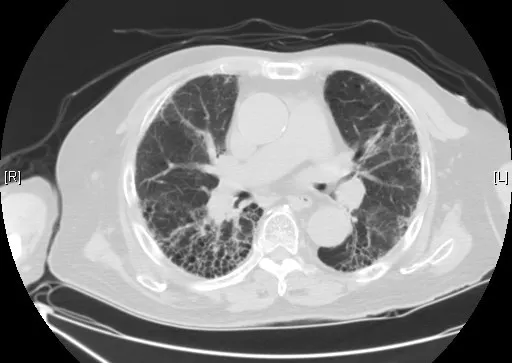

電腦斷層顯示蜂窩狀(honeycombing)變化病灶,看起來像菜瓜布一般。

久咳不癒的二十種可能--14 菜瓜布肺 淺談肺纖維化